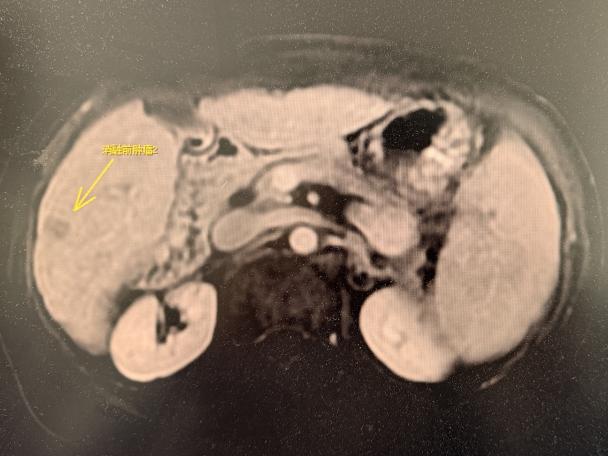

消融术后影像

消融术前影像

陶冀教授表示,对于合并严重基础疾病的高危肝癌患者,微创消融技术与精准围术期管理的有机结合,正在改写传统治疗的“禁区边界”。一直以来,哈医大肿瘤医院深耕高危重症患者的个体化治疗路径,不断探索更安全、有效的治疗模式,为更多肿瘤患者点亮生命之光。